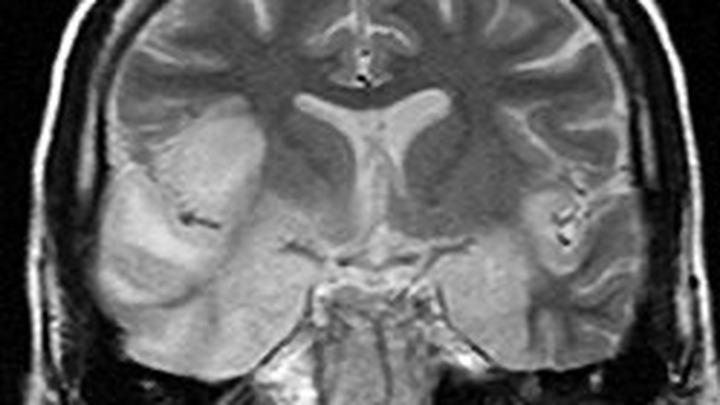

On November 8, 2025, she was rushed to LeBonheur Children's Hospital in Memphis, where she stayed for almost 3 months in ICU in a medically induced coma. On the 40th day she broke through the sedation! She was diagnosed with a rare, life-threatening disease (autoimmune anti-NMDA receptor encephalitis). It causes the body to create antibodies that attack the brain in error, causing the brain to swell and become inflamed. Due to the severe damage done to the brain, she requires neurological rehabilitation, where she is basically learning how to perform the basic functions of life all over again, such as walking, talking, writing, and thinking.